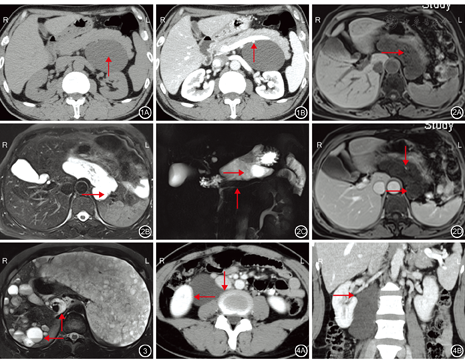

(4)淋巴管瘤的形状:16例患者中,3例淋巴管瘤形态规则,呈类圆形改变(图1),直径均<6 cm;13例淋巴管瘤形态不规则,呈迂曲的囊袋状、管状改变(图2,图3,图4),沿其所在区域间隙生长,具有"塑形"性改变(图2,图4),其中7例淋巴管瘤伸入周围组织间隙,呈"钻缝"样表现(图4)。

(5)淋巴管瘤的内部结构:内容物: 16例患者中,12例行CT平扫检查,病变呈液性低密度(图1A),密度均匀一致,CT值为-10~19 HU;7例行MRI检查T1加权成像(T1 weight image,T1WI)呈低信号(图2A)、T2加权成像(T2 weight image,T2WI)呈高亮信号(图2B),信号基本均匀一致。16例患者腹腔脏器外淋巴管瘤内均未见出血。1例淋巴管瘤病患者肝脏病变内因出血呈"液-液平面"表现(图3)。囊壁及间隔:15例患者淋巴管瘤的囊壁均菲薄、光滑,淋巴管瘤病内部见纤细间隔(图2A、图2B,图3),囊壁及间隔厚度均<2 mm难以测量。1例多房型淋巴管瘤患者囊壁及间隔较厚,且厚薄欠均匀,部分厚度>3 mm,呈等密度,T1WI、T2WI等信号。16例患者淋巴管瘤均未见壁结节、钙化。

(6)淋巴管瘤的边界:16例患者中,15例淋巴管瘤边缘光整,与毗邻组织边界清晰;1例多房型淋巴管瘤与毗邻的十二指肠、胰头部及升结肠边界不清晰(图5)。

(7)淋巴管瘤的毗邻器官关系:16例患者中,10例淋巴管瘤被反挤压而局部内凹,呈弧形压迹(图4)、"脐凹"样表现(图1);4例淋巴管瘤包绕血管(图2D);2例淋巴管瘤内部见脂肪密度或信号(图2)。16例淋巴管瘤均未见包绕肠管,周围均未见肿大淋巴结。

(8)淋巴管瘤的强化模式: 14例行增强扫描患者中,13例淋巴管瘤囊壁及间隔轻度强化(图2D),1例多房型淋巴管瘤中度强化(图5);淋巴管瘤内容物均无强化。

1例多房型淋巴管瘤呈18F-FDG不均匀摄取增加,内部见多发摄取缺损区,高摄取区与囊壁、间隔走行区基本一致,其代谢活性略高于肝脏,SUVmax=3.71,双侧腹股沟淋巴结FDG摄取增加,其余各部位未见明显18F-FDG摄取(图6)。